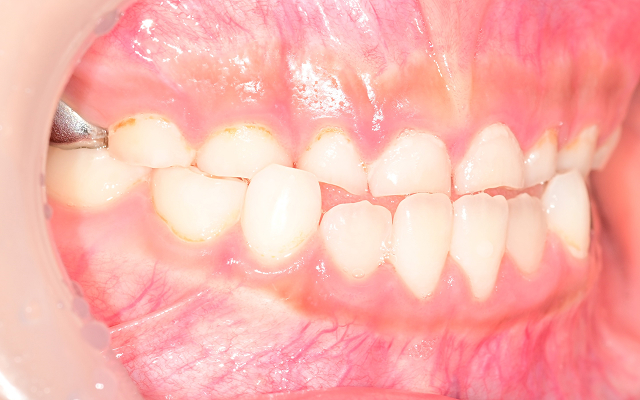

성장기 교정 시기를 놓치면 생길 수 있는 문제

• 01

턱뼈의 성장이 비대칭으로 진행되어 성인 교정 시 수술이 필요할 수도 있음(양악수술)

• 02

영구치가 덧니로 나거나 발치가 필요한 경우로 악화(발치교정)

• 03

교합 불균형으로 턱관절 통증, 비대칭 얼굴선이 생길 수 있음

• 04

입으로 호흡하는 습관이 고착되어 얼굴형이 길어짐